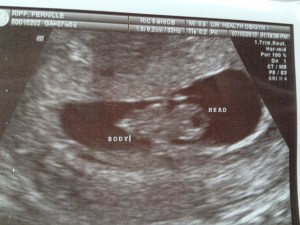

7 weeks ago we got the biggest surprise of our lives; a positive pregnancy test telling us that our 4th child will be joining us at the end of February. While unplanned, this child is so wanted. And so when my body turned against me last week, we thought we had lost our little miracle.

24 agonizing hours later I got to see our little baby kicking , unaffected so far by the hemorrhage that I also have in my uterus. And so begins a fight for this baby and its life. While what I have comes in many forms, it tends to not be a big deal and yet my body has decided to make it a big deal. Just within the last 7 days I have had 3 midwife appointments to check whether the baby is still alive. Every time I have left these appointments so grateful for the fighter that continues to grow within me.